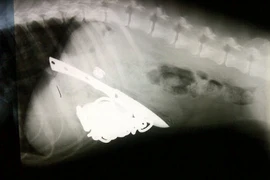

Những dị vật khó tin tìm thấy trong bụng động vật

(Kiến Thức) - Hình ảnh chụp X-quang cho thấy những dị vật khó tin mà bác sĩ thú y lấy ra khỏi bụng động vật, như dao, dây xích, sỏi,...